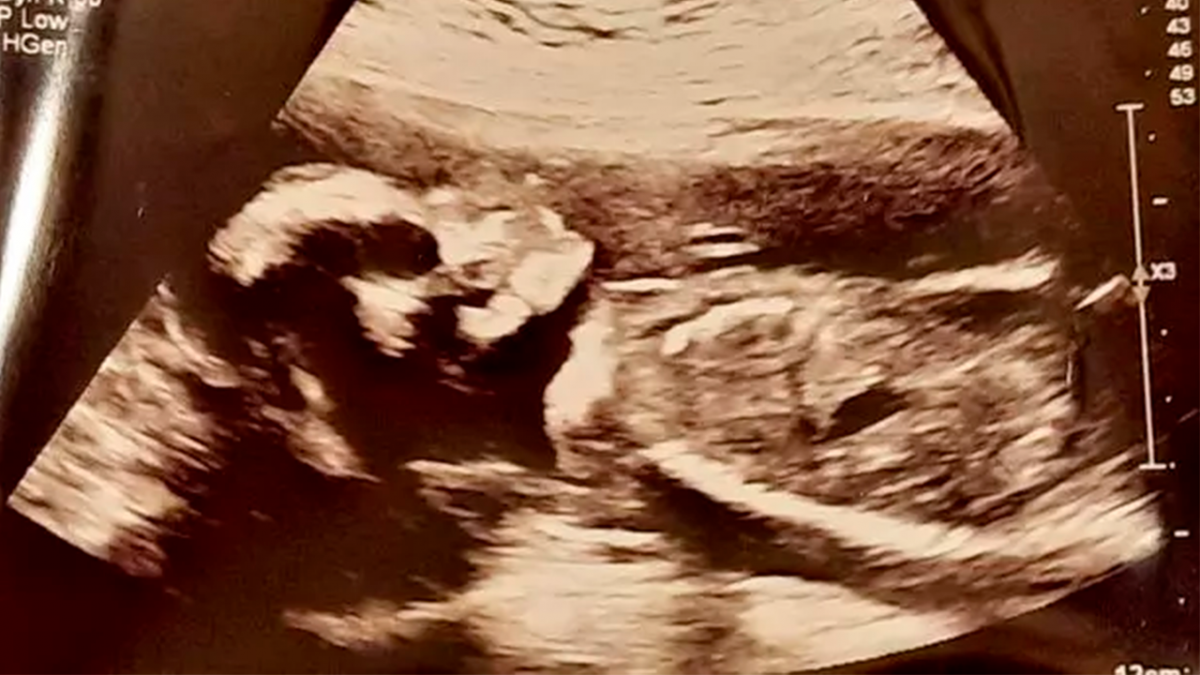

Uma mãe ficou extremamente assustada com a imagem de sua filha no ultrassom na Escócia. Com cinco meses de gravidez aproximadamente, Tasmin Stenhouse, de 25 anos, estava ansiosa para ver o rosto da primeira filha. No entanto, o que antes era empolgação se transformou em desespero quando visualizou uma imagem em preto e branco que mostrava uma “formação craniana diferente”, de acordo com o site de notícias britânico The Mirror.

Inicialmente, o choque se deu por conta das características faciais que eram mostradas na imagem, que se assemelhavam a uma caveira. No entanto, em seguida, o pai da criança deu risada da situação e disse gargalhando que não parecia “tão assustadora”.

A mãe informou que com esse exame eles conseguiram descobrir o sexo da criança. Ela ainda completa que essa foi “uma das primeiras imagens claras que tivemos dela. Mostrei ao meu parceiro e sua reação foi cair na gargalhada”.